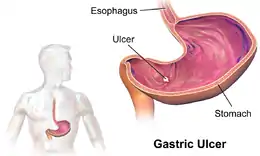

Peptic ulcer disease is a break in the inner lining of the stomach, the first part of the small intestine, or sometimes the lower esophagus.[1][7] An ulcer in the stomach is called a gastric ulcer, while one in the first part of the intestines is a duodenal ulcer.[1] The most common symptoms of a duodenal ulcer are waking at night with upper abdominal pain, and upper abdominal pain that improves with eating.[1] With a gastric ulcer, the pain may worsen with eating.[8] The pain is often described as a burning or dull ache.[1] Other symptoms include belching, vomiting, weight loss, or poor appetite.[1] About a third of older people with peptic ulcers have no symptoms.[1] Complications may include bleeding, perforation, and blockage of the stomach.[2] Bleeding occurs in as many as 15% of cases.[2]

- Esophagus

- Stomach

- Ulcers

- Duodenum

Peptic ulcers are a form of acid–peptic disorder. Peptic ulcers can be classified according to their location and other factors.

By location

- Duodenum (called duodenal ulcer)

- Esophagus (called esophageal ulcer)

- Stomach (called gastric ulcer)

Macroscopic appearance

Gastric ulcers are most often localized on the lesser curvature of the stomach. The ulcer is a round to oval parietal defect ("hole"), 2–4 cm diameter, with a smooth base and perpendicular borders. These borders are not elevated or irregular in the acute form of peptic ulcer, and regular but with elevated borders and inflammatory surrounding in the chronic form. In the ulcerative form of gastric cancer, the borders are irregular. Surrounding mucosa may present radial folds, as a consequence of the parietal scarring.